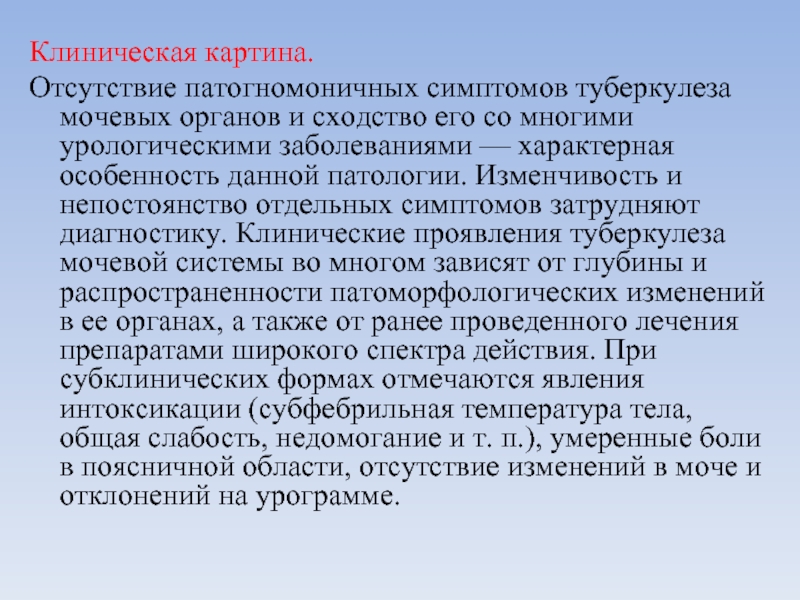

Симптомы и признаки туберкулеза: как распознать заболевание

Раздел: Визуальные уроки